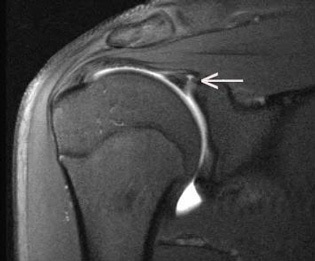

How would you diagnose this T2 MRI image?

SLAP tear